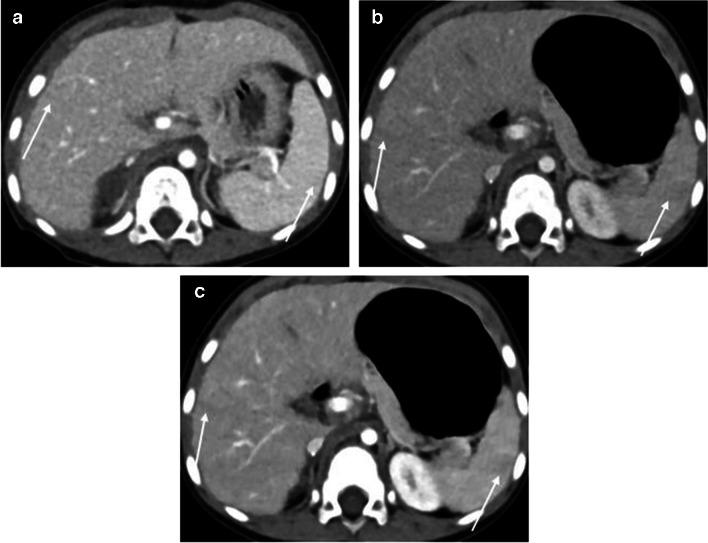

The standard-dose group exhibited higher attenuation, contrast-to-noise ratio (CNR), and signal-to-noise ratio (SNR) of organs and vessels compared to the low-dose group (all P-values < 0.05 except for liver SNR, P = 0.12). However, noise levels did not differ between the standard- and low-dose groups (P = 0.86). The contrast-boosted group had increased attenuation, CNR, and SNR of organs and vessels, and reduced noise compared with the low-dose group (all P < 0.05). The contrast-boosted group showed no differences in attenuation, CNR, and SNR of organs and vessels (all P > 0.05), and lower noise (P = 0.002), than the standard-dose group. In qualitative analysis, the contrast-boosted group did not differ regarding vessel enhancement and lesion conspicuity (P > 0.05) but had lower noise (P < 0.05) and higher organ enhancement and artifacts (all P < 0.05) than the standard-dose group. While iodine uptake was significantly reduced in low-iodine-dose CT (P < 0.001), there was no difference in radiation dose between standard- and low-iodine-dose CT (all P > 0.05).

Low-iodine-dose abdominal CT, combined with an AI-based contrast-boosting technique exhibited comparable organ and vessel enhancement, as well as lesion conspicuity compared to standard-iodine-dose CT in children. Moreover, image noise decreased in the contrast-boosted group, albeit with an increase in artifacts.

与低剂量组相比,标准剂量组器官和血管的衰减、对比噪声比(CNR)和信噪比(SNR)更高(除肝脏SNR外,所有P值均<0.05,肝脏SNR的P值=0.12)。然而,标准剂量组和低剂量组之间的噪声水平没有差异(P=0.86)。与低剂量组相比,造影剂增强组器官和血管的衰减、CNR和SNR增加,噪声降低(所有P<0.05)。造影剂增强组与标准剂量组相比,器官和血管的衰减、CNR和SNR无差异(所有P>0.05),但噪声更低(P=0.002)。在定性分析中,造影剂增强组在血管强化和病变清晰度方面无差异(P>0.05),但与标准剂量组相比,噪声更低(P<0.05),器官强化和伪影更高(所有P<0.05)。虽然低碘剂量CT中的碘摄取显著降低(P<0.001),但标准碘剂量CT和低碘剂量CT之间的辐射剂量没有差异(所有P>0.05)。

与儿童标准碘剂量CT相比,低碘剂量腹部CT联合基于AI的造影剂增强技术在器官和血管强化以及病变清晰度方面表现相当。此外,造影剂增强组的图像噪声降低,尽管伪影有所增加。